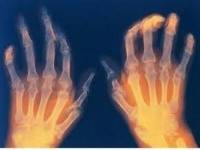

รูมาตอยด์ คือ โรคข้ออักเสบชนิดหนึ่ง ที่เกิดขึ้นได้กับคนทุกเพศทุกวัย ส่วนใหญ่จะรักษาไม่หายและถ้าได้รับการรักษาช้าอาจทำให้ข้อถูกทำลายได้ แต่หากได้รับการรักษาอย่างถูกต้องตั้งแต่ต้น ผู้ป่วยก็สามารถจะอยู่กับโรคนี้ได้อย่างมีความสุข นางสาวนิภาวรรณ ปรมาธิกุล ผู้อำนวยการกลุ่มวิจัยและพัฒนานิวเคลียร์ สถาบันเทคโนโลยีนิวเคลียร์แห่งชาติ (องค์การมหาชน) หรือ สทน. บอกว่าปกติการรักษาโรครูมาตอยด์ทำได้ 3 วิธี วิธีแรก คือ รักษาโดยการผ่าตัด แต่มีข้อเสีย อาจทำให้กระดูกผุกร่อน และโรคสามารถกลับมาเป็นใหม่ได้อีกครั้ง วิธีที่สอง คือ รักษาโดยการใช้ยา ซึ่งมีข้อจำกัดในการใช้ เนื่องจากถ้าใช้ยาที่มีขนาดเกินขีดกำหนด จะมีผลเสียต่อระบบภายในร่างกาย และ วิธีสุดท้าย คือ การรักษาด้วยเภสัชรังสี โดยรังสีสามารถเข้าไปทำลายเนื้อเยื่อโดยรังสีจะสามารถทำลายเนื้อเยื่อส่วนที่เกิดการอักเสบ และสามารถใช้ในการรักษาตั้งแต่ระยะเริ่มต้นและระยะเรื้อรังได้ ซึ่งล่าสุดสทน. โดยความร่วมมือของนักวิจัยด้านเภสัชรังสีและศูนย์ไอโซโทปรังสี ประสบความสำเร็จในการวิจัยและผลิตเภสัชรังสี เพื่อรักษาโรครูมาตอยด์ โดยสามารถผลิตเภสัชรังสี สำหรับรักษาโรคดังกล่าวได้ถึง 2 ตัว ได้แก่ ซาแมเรียม-153 เฮชเอ (153Sm-HA) และ อิตเทรียม-90 ซิเตรท คอลลอยด์ (90Y-citrate colloid) ซึ่งจัดเป็นยาฉีดเพื่อใช้สำหรับการนำมารักษาโรครูมาทอยด์ ตั้งแต่ระยะเริ่มต้นและระยะเรื้อรังได้ตามลำดับ ด้านนางอังคนันท์ อังกุรรัตน์ หัวหน้าฝ่ายวิเคราะห์คุณภาพ ศูนย์ไอโซโทปรังสี บอกว่า ซาแมเรียม-153 เฮชเอ เป็นยาฉีดที่มีความบริสุทธิ์ทางเคมีรังสีมากกว่า 90% มีความคงตัว 2 วัน มีความเป็นกรดเบส (pH) = 4-7 มีความปลอดเชื้อ และปลอดพิษ ส่วน อิตเทรียม-90 ซิเตรท คอลลอยด์ เป็นยาฉีดที่มีลักษณะเป็นสารคอลลอยด์สีขาวขุ่น โดยมีความบริสุทธิ์ทางเคมีรังสีมากกว่า 95% มีความคงตัว 15 วัน มีความเป็นกรดเบส (pH) = 5.5-7 มีความปลอดเชื้อ และปลอดพิษ เนื่องจาก อิตเทรียม-90 ซิเตรท คอลลอยด์ มีลักษณะเป็นคอลลอยด์ ซึ่งเป็นข้อดีสำหรับการฉีดสารดังกล่าวเข้าข้อต่าง ๆ และช่วยให้การกระจายตัวของยาไปยังบริเวณเยื่อหุ้มไขข้ออักเสบได้ทั่วถึง ทำให้มีประสิทธิภาพของการรักษาได้ดี แต่อย่างไรก็ตามสนท.บอกว่า อิตเทรียม-90 มีข้อเสียคือ ให้เฉพาะอนุภาคบีตา เพราะฉะนั้นในการติดตามและวัดปริมาณของรังสีจะทำได้ยากกว่า ซาแมเรียม-153 ซึ่งให้รังสีแกมมาและบีตาพร้อมกัน แต่การวัดปริมาณรังสีฮิตเลียม -90 สามารถแก้ไขโดยอาศัยการวัดเนื่องมาจากการเกิดรังสีแม่เหล็กไฟฟ้าทดแทนได้ ซึ่งมีผลทำให้การรักษาโรครูมาตอยด์ได้อย่างมีประสิทธิภาพดีขึ้น . นาตยา คชินทร nattayap.k@gmail.com